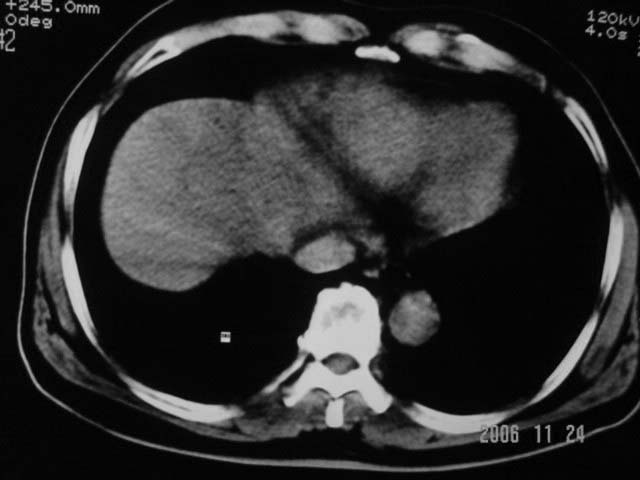

标题: CT5395:男、60岁,皮肤、巩膜黄染伴上腹部疼痛20天 [打印本页]

标题: CT5395:男、60岁,皮肤、巩膜黄染伴上腹部疼痛20天

劳烦各位老师看一下最后一幅箭头指的地方是不是胆总管结石.ct值约63hu.

感觉不是结石可能,与上一层面联系应该是门脉区影像,图像显示不佳,胆总管显示不清[特别是胰头以上段],目前影像只能说肝内外胆管扩张,胰管扩张,胆囊扩大。提示胆总管远端梗阻。可考虑肿瘤或结石所致

胆总管内结节状高密度灶,边缘隐约可见低密度环绕,首先考虑结石伴肝内胆管扩张; 2、胆囊增大,胆囊炎

肝内外胆管及胰管均示有扩张,胆囊增大.提示胆总管远端梗阻,可考虑肿瘤或结石或肿瘤伴结石,建议强化扫描